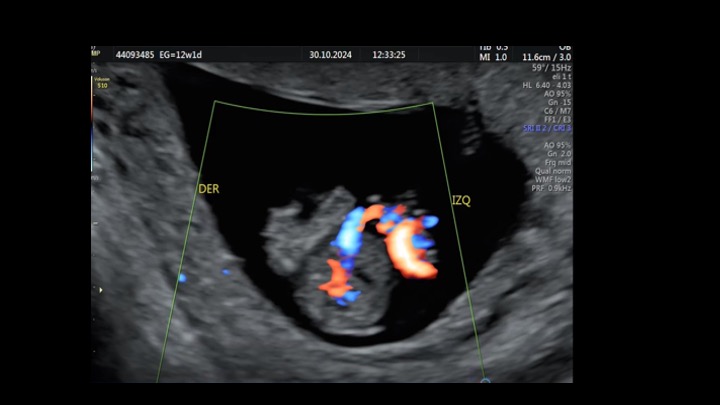

Se presenta el caso de una paciente de 23 años de edad, secundigesta, sin antecedentes personales ni familiares de relevancia. La paciente adjunta el estudio de screening de aneuploidías de la semana 11-14, que arroja bajo riesgo. Las imágenes 1 y 2 describen los hallazgos identificados durante la evaluación de la anatomía fetal en la semana 12. Las imágenes 3, 4 y 5 corresponden a los controles ecográficos posteriores, del segundo y tercer trimestre. La imagen 6 muestra al recién nacido. Seleccione la opción correcta: A. Corresponde a una hernia umbilical fisiológica con resolución más tardía. B. Corresponde a una gastrosquisis con cierre espontáneo intraútero. C. Corresponde a un onfalocele con ruptura del mismo. D. El defecto de pared cerró espontáneamente mejorando el pronóstico y riesgo de complicaciones gastrointestinales. Figura 1: se visualiza corte axial del abdomen fetal, a nivel de la inserción del cordón umbilical, con Doppler color en semana 12. Figura 2: se observa corte axial, a nivel de la inserción del cordón umbilical en la pared abdominal anterior, en semana 12. Figura 3: corte sagital a nivel de la inserción del cordón en la pared abdominal anterior, con Doppler color, en semana 20. Figura 4: corte axial del abdomen fetal, en semana 32, donde se identifica dilatación de las asas intestinales. Figura 5: corte axial del abdomen fetal, en semana 32, donde se identifica dilatación de las asas intestinales, con la utilización del Doppler color. Figura 6: se observa al recién nacido.

El caso presentado corresponde a una paciente de 23 años, secundigesta, sin antecedentes personales de relevancia, con embarazo único y espontáneo, que concurre al consultorio de ecografía para realizar un screening combinado del primer trimestre en la semana 12. Se evidencia solución de continuidad en la pared abdominal anterior, adyacente al cordón umbilical, con exteriorización de asas intestinales, compatible con gastrosquisis (Figuras 1 y 2).